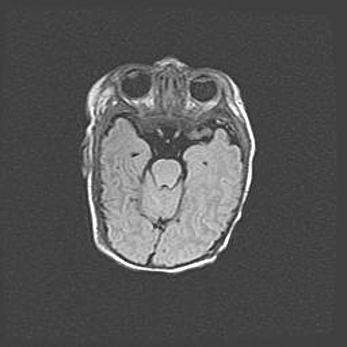

Открытая гидроцефалия.

Возраст: 9 месяцев 12 дней

Вес: 6800 г

Пол: мужской

Окружность головы: 41,5 см

Срок гестации: 28 недель

Гидроцефалия головного мозга у новорожденных имеет характерный признак: опережающий рост окружности головы приводит к визуально хорошо определяемой гидроцефальной форме сильно увеличенного в объёме черепа. Детские неврологи определяют следующие симптомы гидроцефалии у грудничков: выбухающий напряжённый родничок, частое запрокидывание головы, смещение глазных яблок к низу.